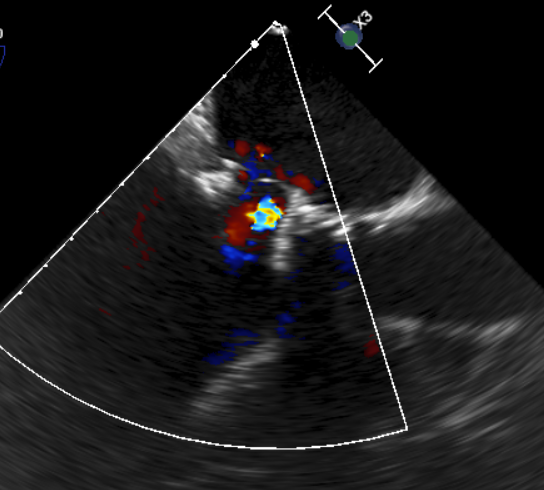

CDFI提示过瓣血流通畅

CDFI示少量瓣周漏

收缩期未见瓣周漏